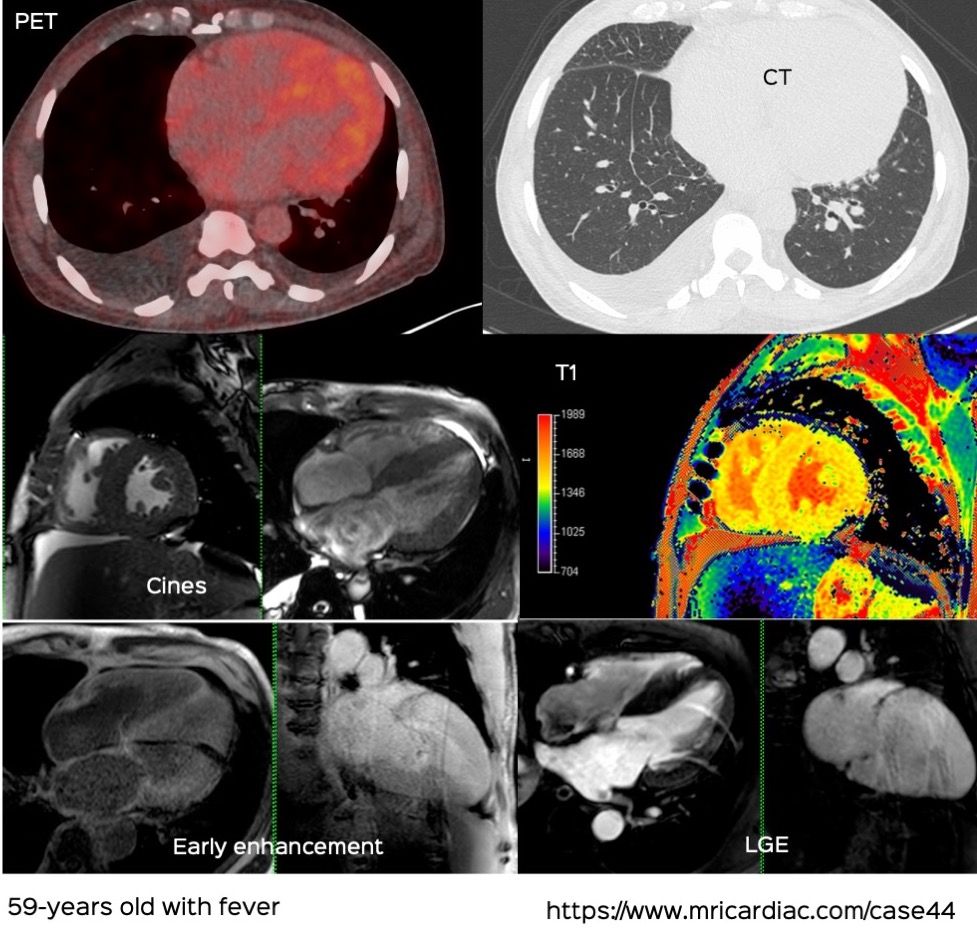

83-years old presented with HFrEF in June 2025, echo showing LVH with reduced EF.

Cardiac MRI shows typical findings of amyloidosis with diffuse transmural enhancement, deranged contrast kinetics and raised T1 and an ECV of 60%.

The video discusses the case and the importance of T1 and ECV, specifically based on a new JACC article that I read yesterday (Sheikh A et al - JACC 2026 Vol 87, pg 505), published a day prio that discusses the importance of ECV in quantifying transthyretin amyloidosis.